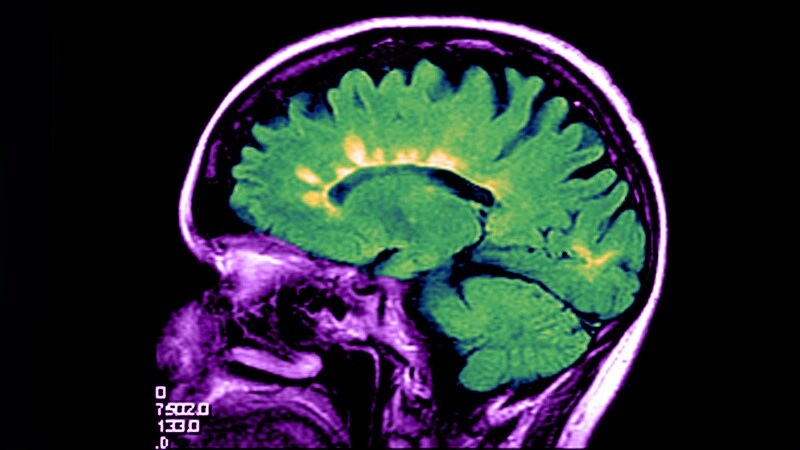

Multiple Sclerosis